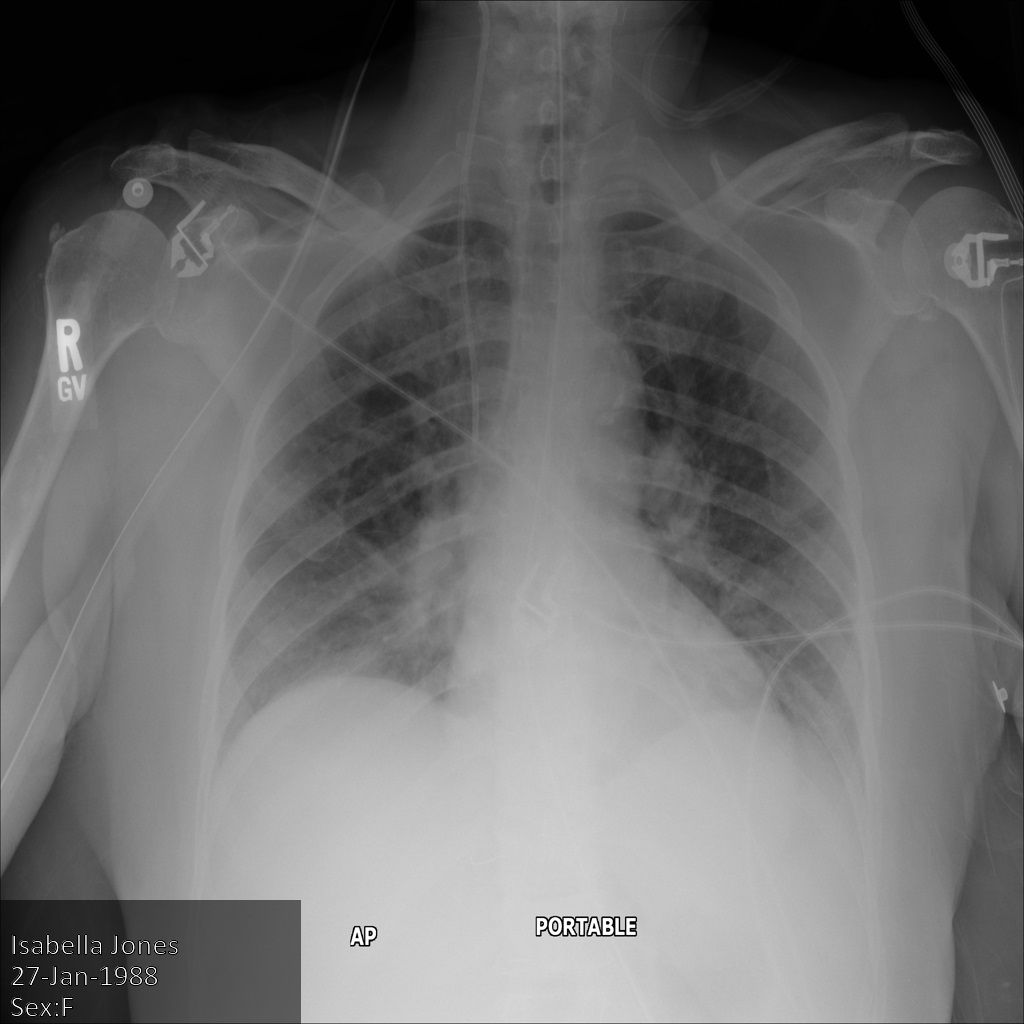

Gambar berikut menunjukkan hasil rontgen pasien yang tidak disamarkan:

Setelah mengirimkan gambar ke Cloud Healthcare API menggunakan opsi REDACT_SENSITIVE_TEXT, gambar akan muncul sebagai berikut:

Anda dapat melihat bahwa hal berikut terjadi:

PERSON_NAMEdi kiri bawah gambar disamarkanDATEdi kiri bawah gambar disamarkan

Jenis kelamin pasien tidak disamarkan karena tidak dianggap sebagai teks sensitif menurut infoType DICOM default.